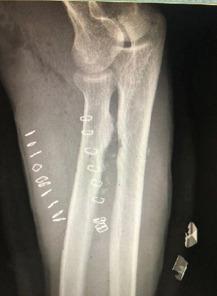

一名35岁男性木匠主诉右前臂旋后和旋前受限8个月,肘部区域疼痛轻微,既往无创伤或手术史。检查发现,前臂旋后和旋前运动完全受限,肘部屈伸正常,无神经血管缺损。右桡尺骨及肘部X线显示,在桡骨结节水平的桡骨近端和尺骨之间存在融合。采用前后联合入路切除融合。术后患者旋后和旋前运动良好,无疼痛,职业活动无困难。